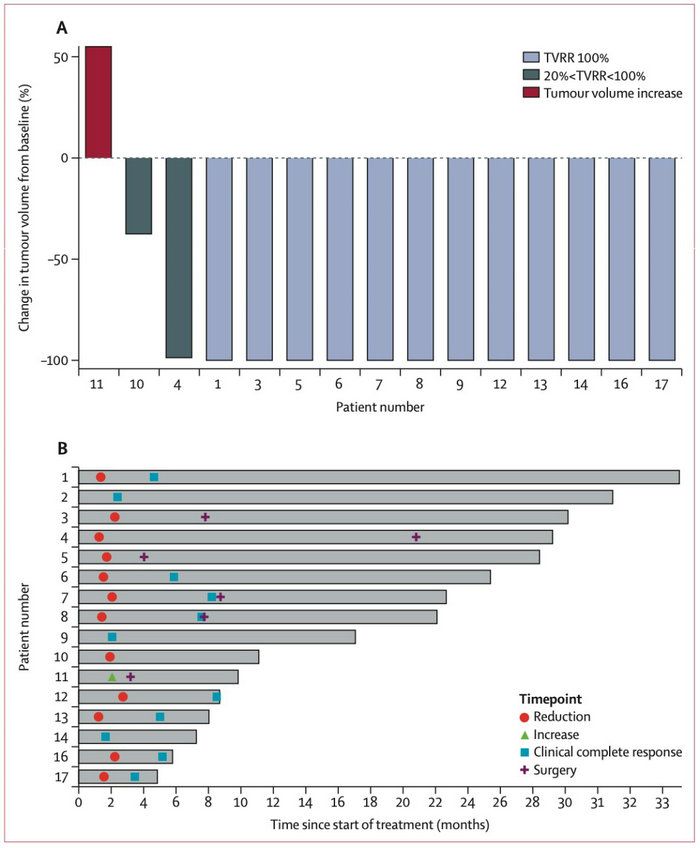

研究共入組了17例初診dMMR/MSI-H局部晚期直腸癌患者,在16例可評估療效的患者中有15例的腫瘤在治療后縮小。其中,6例患者接受了根治性手術,有3例達到病理完全緩解;9例患者達到臨床完全緩解并選擇了隨訪觀察,從而避免了放化療及手術的損傷;1例患者因不良反應提前終止治療。研究總的完全緩解率高達75%。此外,本研究中患者達到臨床完全緩解的中位時間為5.2個月,提示和傳統的新輔助放化療相比,免疫治療可能需要較長的時間才能達到最佳療效。在毒副作用方面,觀察到的不良反應大多數為1-2級,僅發生1例3級以上不良事件。這組病人隨訪到2022年11月,均未出現腫瘤復發。

信迪利單抗在dMMR/MSI-H局部晚期直腸癌中的療效和持續時間